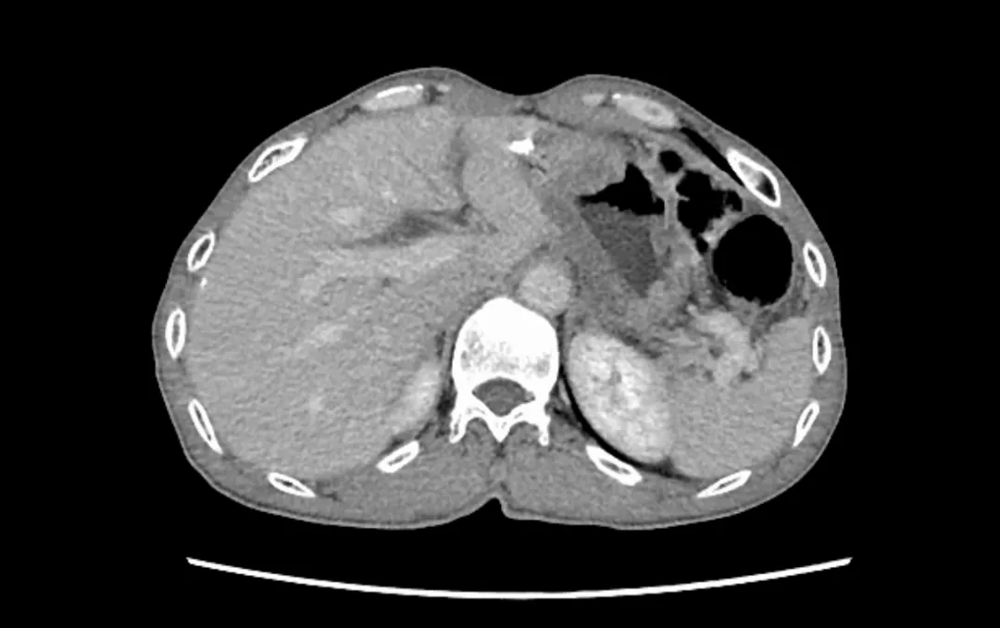

针对肾上腺肿瘤等腹膜后复杂占位,泌尿外科团队熟练掌握腹腔镜微创技术。近期,一例因体检发现肾上腺占位的患者,经影像评估与内分泌检查,高度怀疑嗜铬细胞瘤。团队充分进行术前扩容降压准备,成功实施“腹腔镜下左侧肾上腺全切术”。术后病理确诊为嗜铬细胞瘤(恶性潜能)。此类手术风险高、操作精细,我院团队凭借娴熟技术,实现了肿瘤完整切除,患者恢复良好,彰显了在复杂内分泌肿瘤微创手术领域的专业能力。